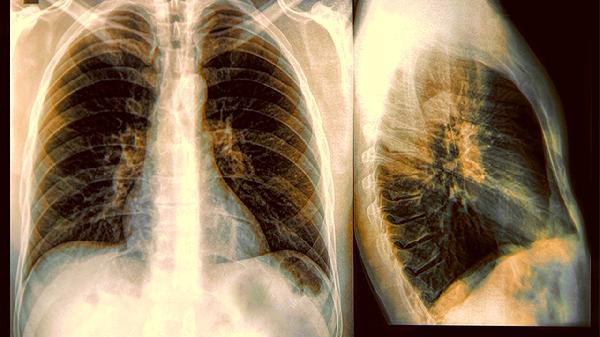

肺结节就像是肺部拍X光时发现的小斑点,它们的直径通常不超过三厘米。就像脸上突然冒出的痘痘,绝大多数情况下都是无害的。

医生会通过观察结节的大小、边缘是否光滑、密度等特征来评估风险。那些形状不规则、边缘毛糙的结节需要格外关注。